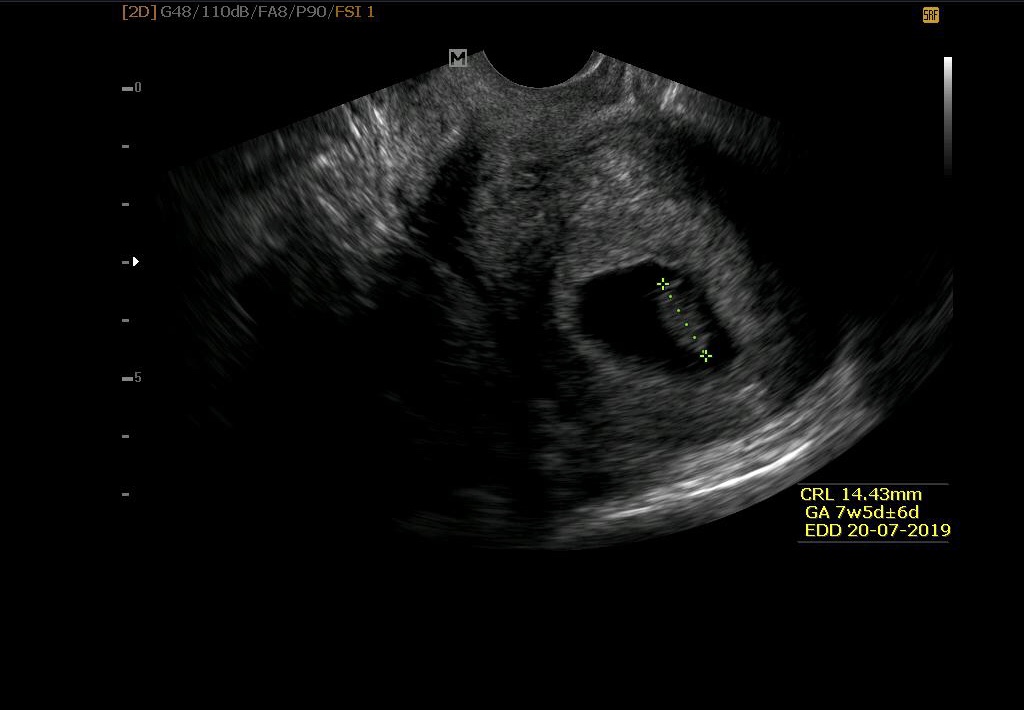

včera jsem byla na ultrazvuku, měla bych být dle menstruace 7+6 a podle doktora i velikost plodu odpovídá 8 týdnu. Pročítala jsem nějaké články a plod v 8 tt by měl měřit až 3 cm a v 9 tt až 6 cm..mne byl naměřen necelých 15 mm-1,5 cm na konci 8 tt..trošku se bojím, že je moc malinkej a jestli je všechno vporadku..dle doktora od posledního ultrazvuku pekne vyrostl (předchozí ult. 4,5 mm). Měla jste to některá podobně? Děkuji za rady😊

6 cm v 9tt je blbost. To jsem měla na začátku 13.tt a přesně to odpovídalo. Takže klid, mimčo má správnou velikost 😊

Co jste četla je blbost,u mě na screeningu 13+3 mělo malé 7cm těžko by mělo 6cm v 9tydnu,na konci 8 tydne má kolem 1cm

@natalia1216 ve čtvrtek jsem byla na kontrole 10+4 dle UTZ, uzlík měl 3,65 cm 😊👍🏼